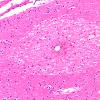

MYELIN (NON-IMMUNE MEDIATED)

Fat Embolism (12)